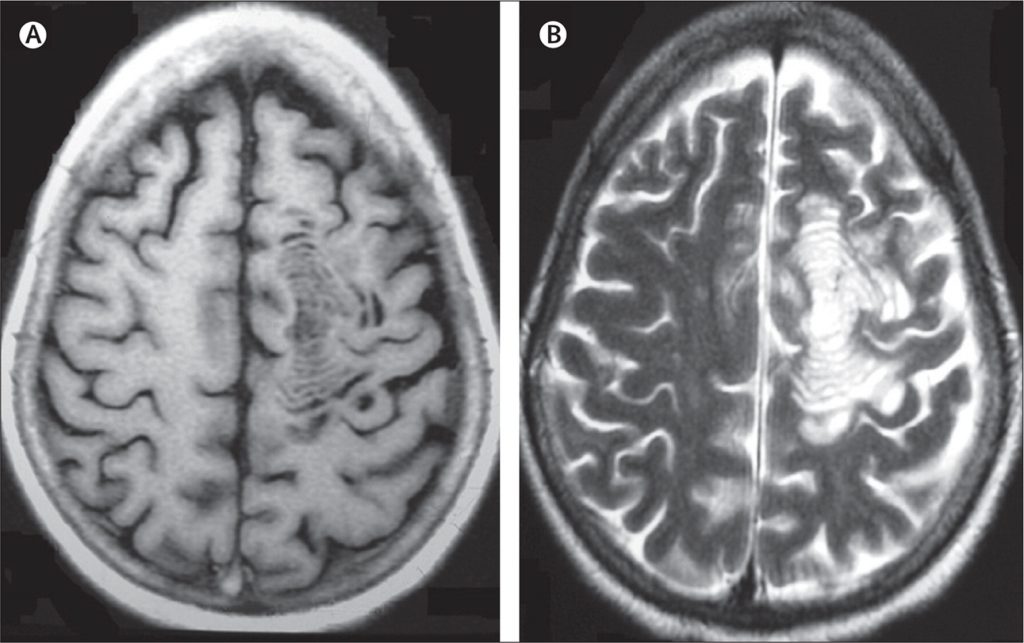

بیماری شیلدر : کودکان و مولتیپل اسکلروزیس